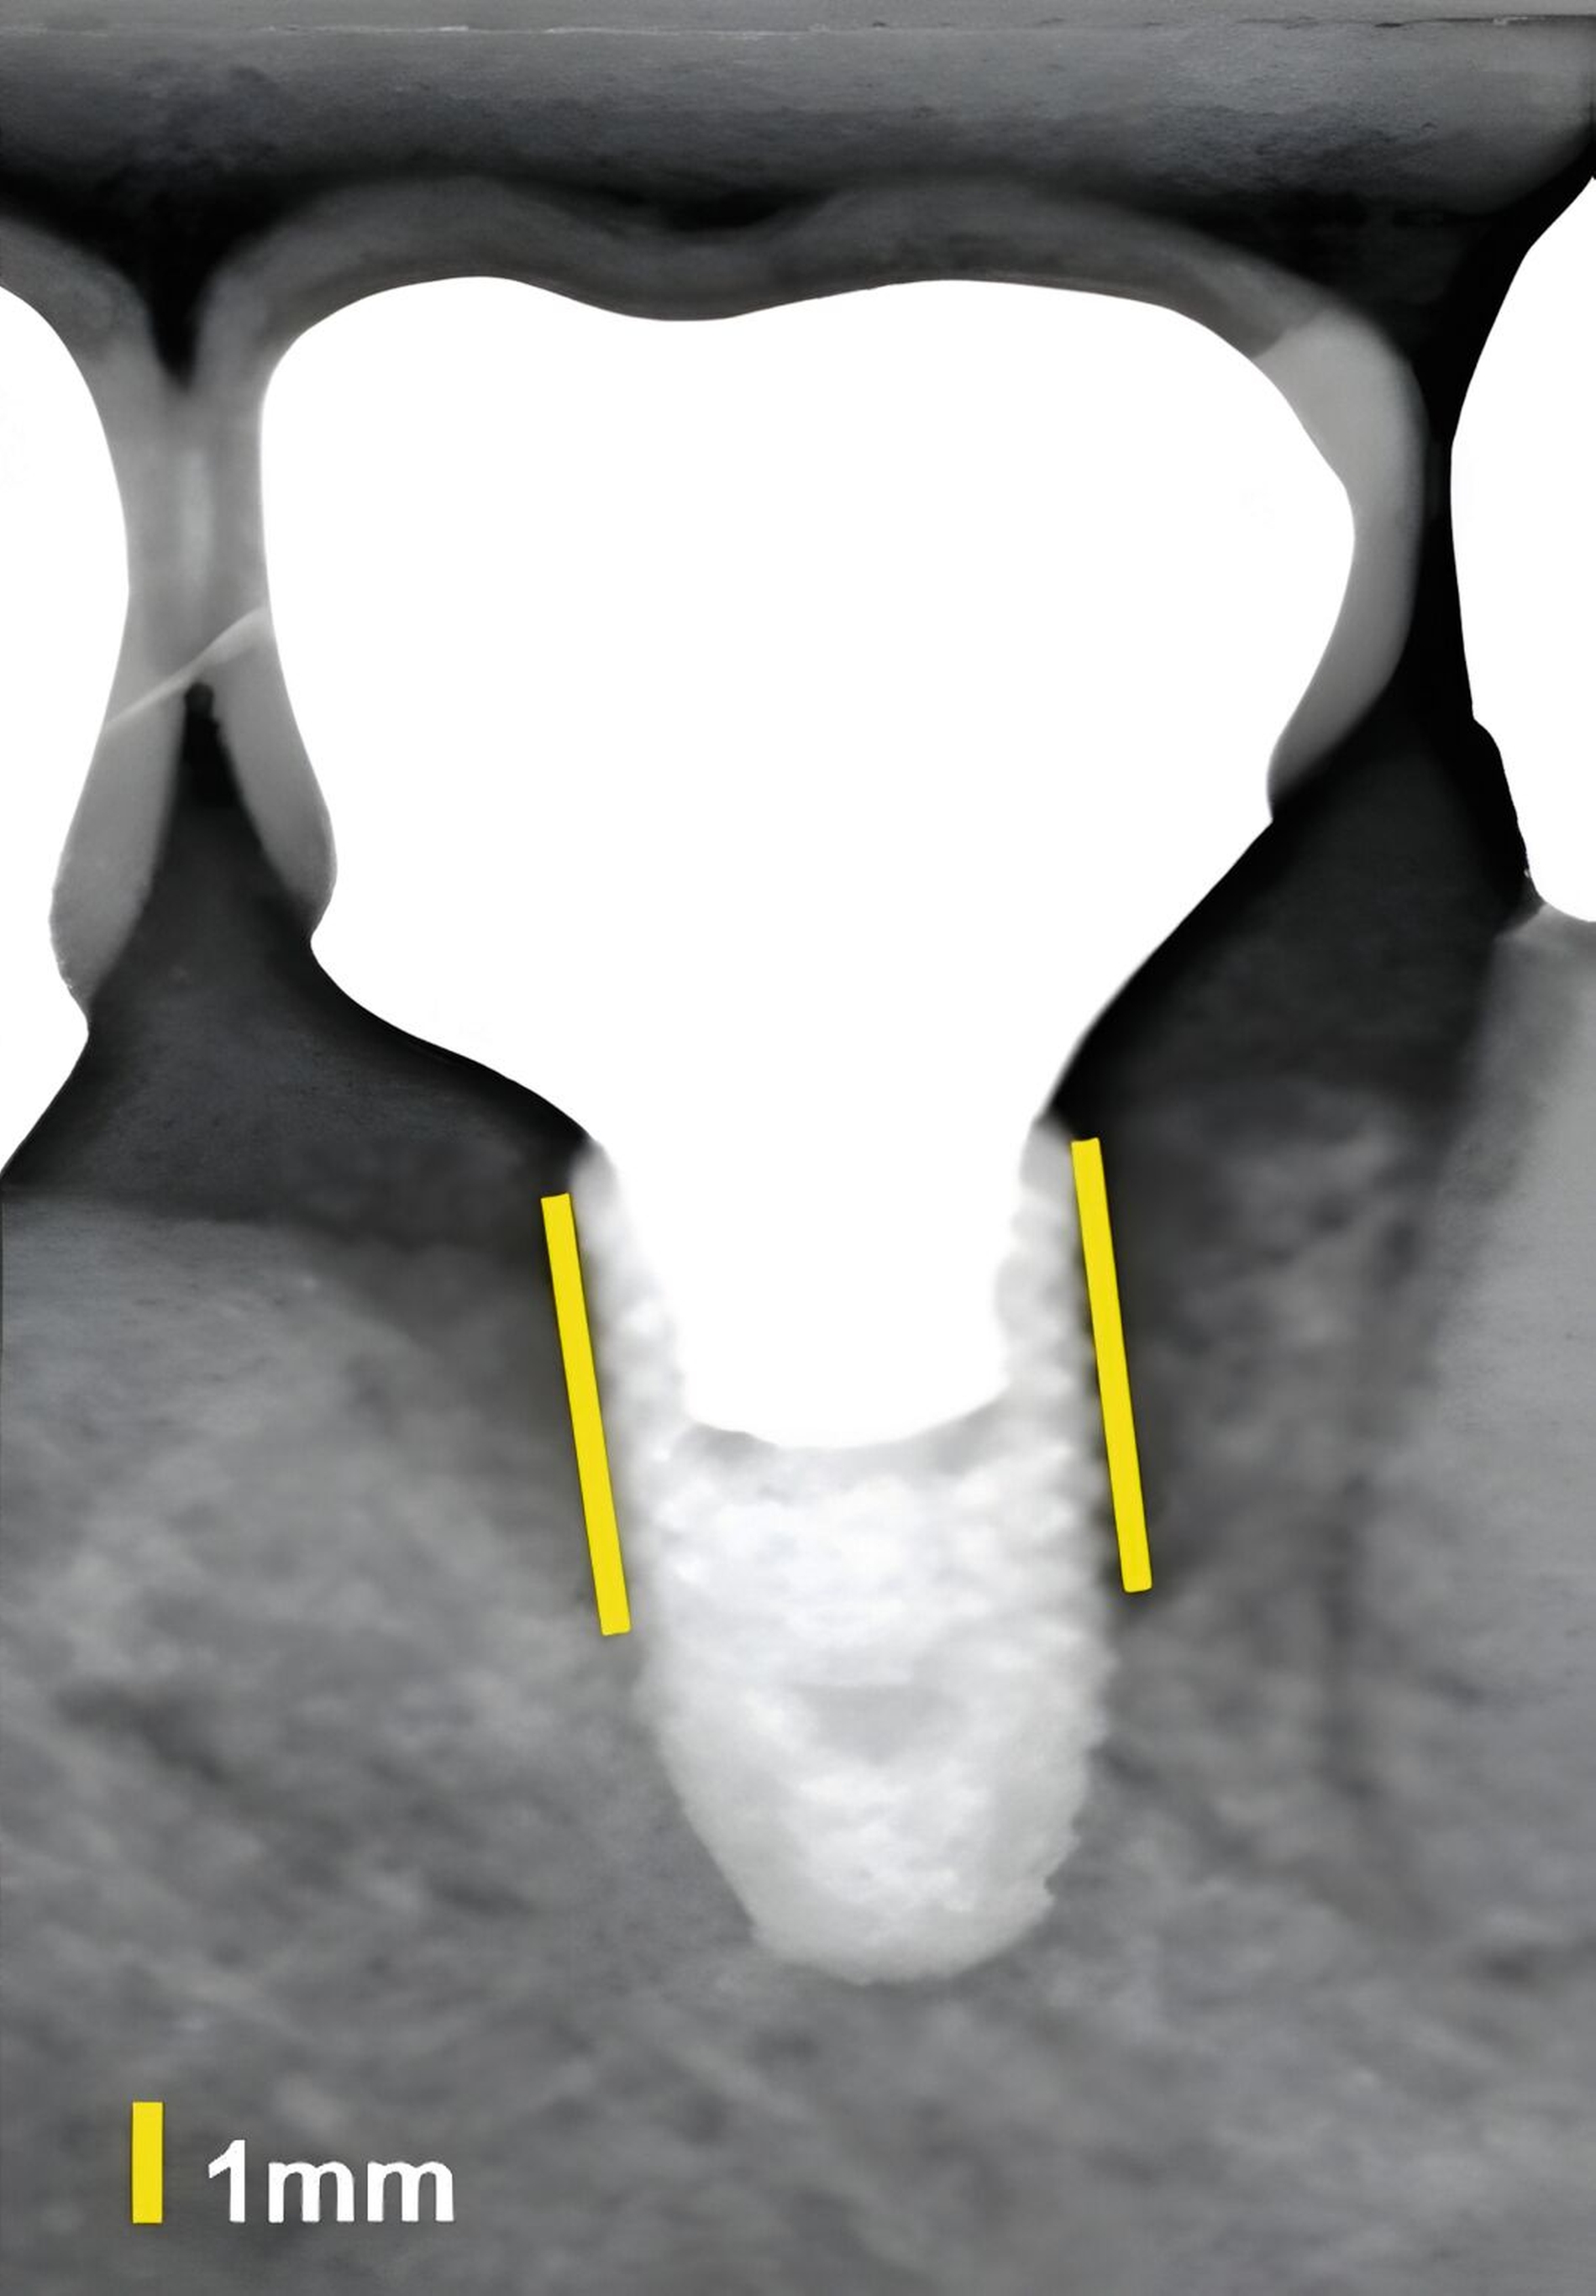

An Zähnen und Implantaten konnten das krestale Knochenniveau und die Weichgewebsdimension exakt anatomisch dargestellt werden (Abbildungen 3 und 4). An Implantaten erfolgte in einer humanen Kadaverstudie der Vergleich zwischen US- und direkten Messungen in Bezug auf die Höhe und die Dicke des Knochenniveaus und des Weichgewebes [Chan et al., 2018]. Die Korrelationen zwischen den US- und den direkten Messungen reichten von 0,92 bis 0,98 (p < 0,0001).

In einer eigenen klinischen Fallserien-Studie an Patienten mit Implantaten konnte erstmals gezeigt werden, dass auch periimplantäre Knochendefekte (Dehiszenzen, Fenestrationen, dreiwandige Defekte) sonografisch vermessen werden können [Thöne-Mühling et al., 2012] (Abbildung 5).

Dies konnte in einer ebenfalls eigenen humanen Kadaverstudie bestätigt werden [Bykhovsky et al., 2024]. Dabei wurden an Implantaten standardisiert Fenestrationen (n = 7), Dehiszenzen (n = 14) und dreiwandige Knochendefekte (n = 6) präpariert (Abbildungen 6 bis 8). Die Defekte wurden mit US- und DVT-Aufnahmen untersucht und die Messungen mit den direkten Messungen verglichen. Die US-Messungen zeigten eine starke Korrelation mit den direkten und den DVT-Messungen. Die sonografische Messgenauigkeit war bei Dehiszenzen am höchsten, gefolgt von Fenestrationen und dreiwandigen Knochendefekten.